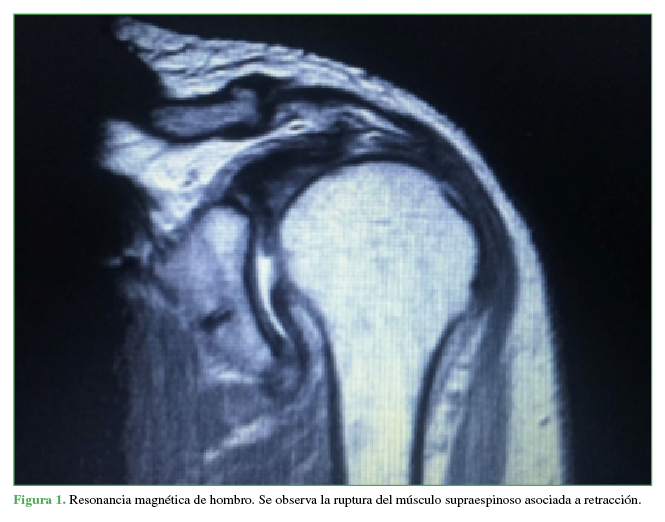

Introducción: La prevalencia del dolor de hombro oscila entre el 6,7% y el 66,7%; los trastornos del manguito rotador y especialmente la ruptura pueden alcanzar una prevalencia del 22,1%. Debido a los importantes avances y estudios en la reparación de esta lesión, la cirugía artroscópica ha permitido una mejor identificación, visualización y clasificación, y un mejor manejo de los pacientes. Además, la ruptura del manguito rotador o la fractura de la tuberosidad mayor del húmero incrementan el riesgo de lesión nerviosa (riesgo relativo –1,9), más significativa en pacientes >60 años. Se presenta a un paciente con ruptura postraumática del manguito rotador, quien requirió reparación artroscópica mínimamente invasiva, con evolución posoperatoria estacionaria y diagnóstico de lesión del nervio axilar, sin recuperación autolimitada atribuida a luxación anterior e inestabilidad secundaria altrauma inicial.Conclusiones: La lesión del nervio axilar es más frecuente que lo esperado y, en muchas ocasiones, la identificación temprana se pasa por alto debido a la alta asociación con otras lesiones. Por lo tanto, el diagnóstico y el manejo oportunos requieren mucho cuidado por parte del médico tratante. AbstractIntroduction: The prevalence of shoulder pain varies between 6.7% and 66.7%; whereas rotator cuff disorders–especially rupture–can reach a prevalence of 22.1%. Due to the important advances and studies in the repair of this injury, arthroscopic surgery has allowed a better identification, visualization and classification, as well as a better handling of the patients. In addition, rotator cuff ruptures or greater tuberosity fractures increase the risk of nerve injury (relative risk -1.9), which is more significant in patients >60 years old. We discuss the case of a patient with post-traumatic rotator cuff rupture who required minimally invasive arthroscopic repair. No weight-bearing was allowed during the postoperative period. Patient presented a non-self-limited axillary nerve injury secondary to anterior dislocation and resulting instability after the original trauma.Conclusions: Axillary nerve injuries are more common than expected and, in many cases, early identification is not possible due to its high rate of association with other injuries. Therefore, treating physicians must be very careful in order to achieve a timely diagnosis and management of the patient.Descargas